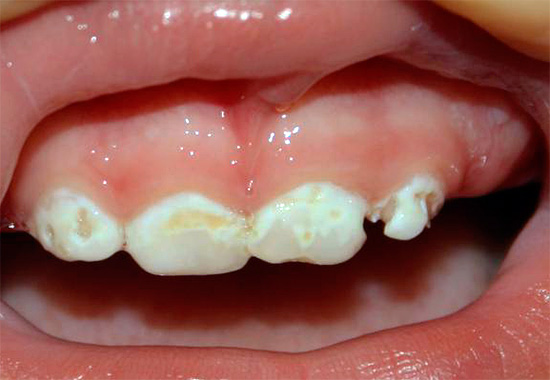

La carie viene mostrata nella prima fase di sviluppo quando si tratta di un punto bianco o gessoso (ecco come appaiono le aree dello smalto demineralizzato):

Nella foto: la carie in una fase iniziale di sviluppo:

Questo stadio di sviluppo della patologia è chiamato stadio del punto bianco: qui si verifica solo il danno iniziale allo smalto e la formazione di pori in esso sotto l'influenza di acidi aggressivi dalla cavità orale. Lo smalto perde la sua lucentezza, acquisisce un colore bianco più chiaro e saturo.

Ecco alcune altre foto di carie sul palco spot: